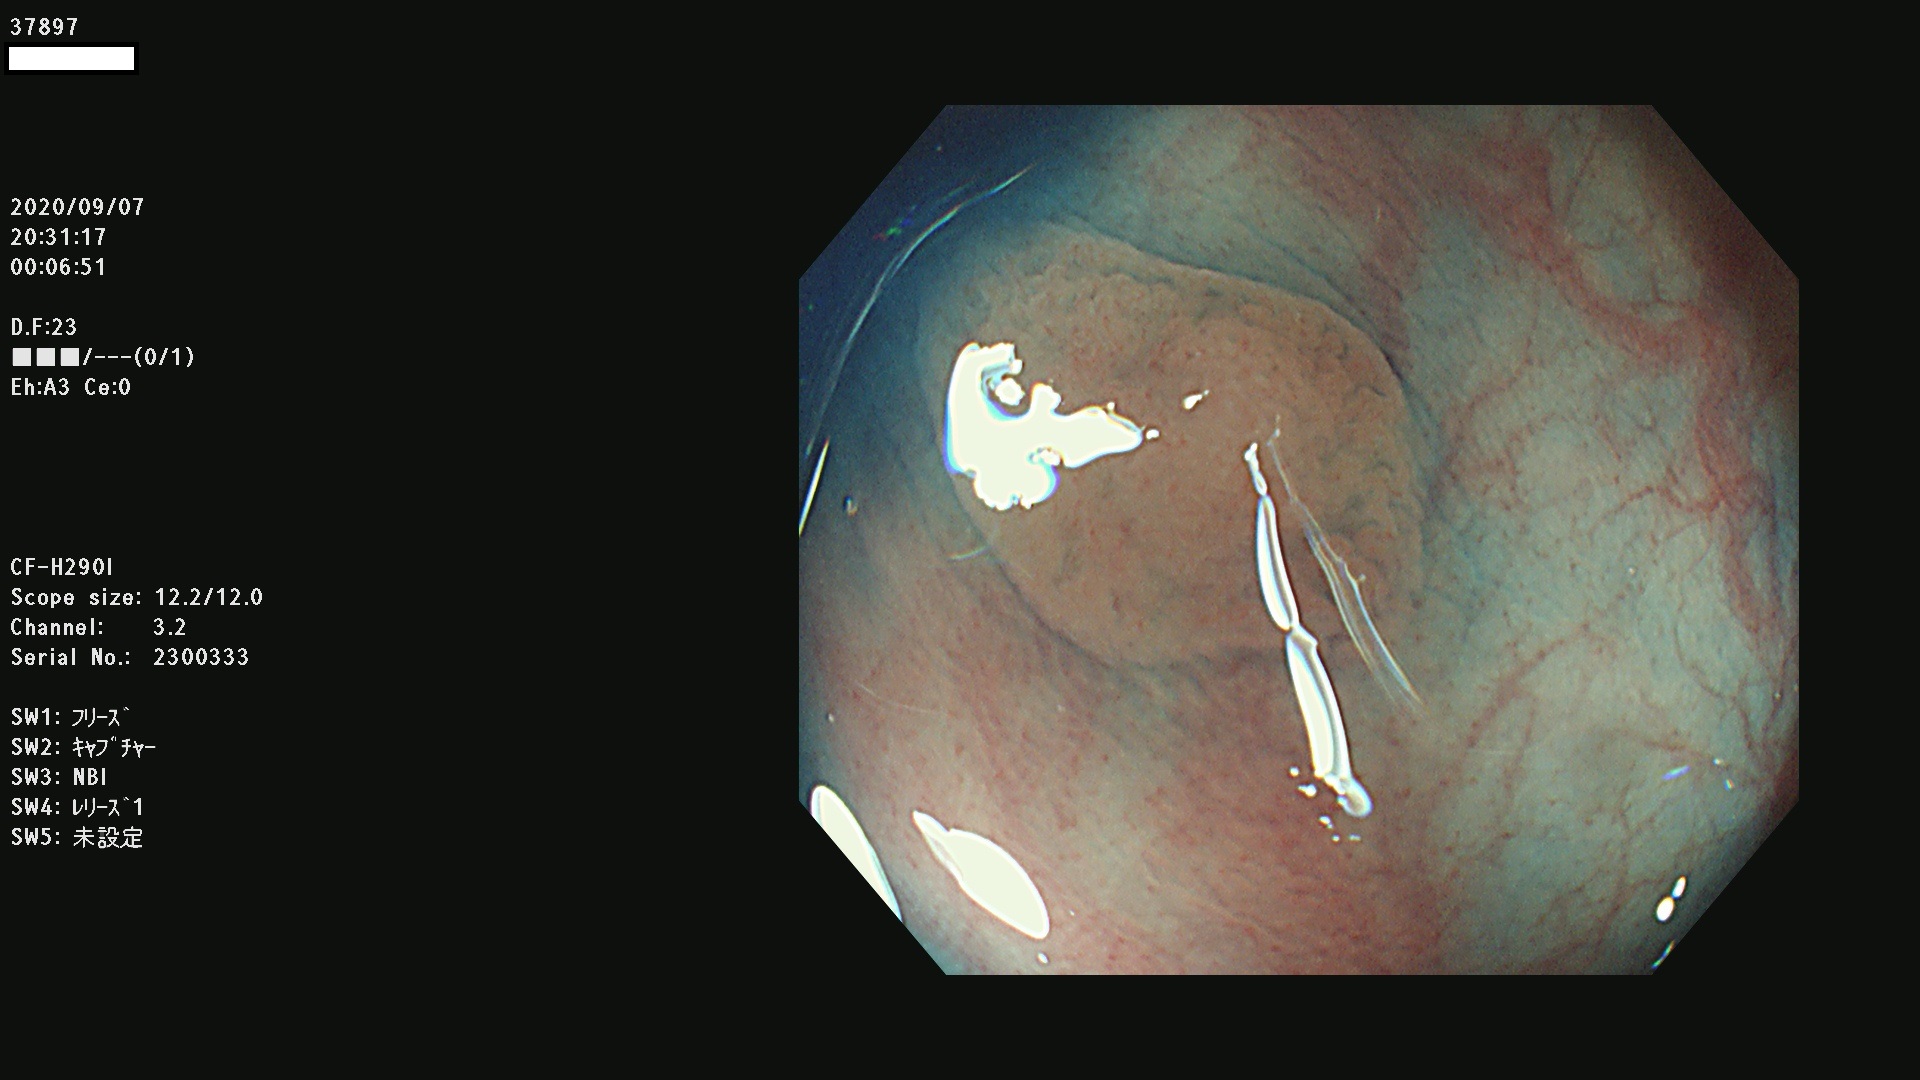

腺腫発見率 75 % (カルテ番号 37800〜37899の100名の方の検査結果で集計)大腸癌検診最新情報

以下のカルテ番号の方に腺腫(Adenoma,Group3〜5)が見つかりました(集計法)

37800(SSAPのみ) 37801 37802 37803 37804 37805 37806 37807 37808 37809(SSAPのみ) 37810 37811 37812 37813 37814 37815 37817 37818 37819 37820 37821 37822 37824 37825 37826 37827 37828 37829 37832 37833 37836 37837(SSAPのみ) 37839 37840 37842 37844 37845(SSAPのみ) 37847 37849 37850 37851 37852 37853(SSAPのみ) 37855 37856 37857 37860 37861 37862 37863 37864 37867 37868 37871 37874 37876 37877 37879 37880 37881 37882 37883 37886 37887 37888 37889 37890 37891 37892 37893 37894 37896 37897 37898 37899

発見困難で危険性の高い平坦型病変(上記100名より抽出) ![]()